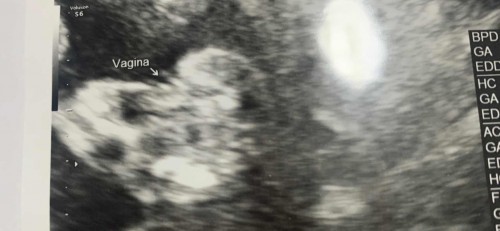

ไปซาวมาตอนอายุครรภ์ 17 วีค 5 วัน คุณหมอบอกได้ผู้หญิงค่ะ แบบนี้ 100% เลยมั้ยคะ ตอนนี้ 20 วีคแล้วค่ะ #ขอบคุณล่วงหน้านะคะ

เขียน+ลูกศรจิ้ม แบบนี้ หมอต้องมั่นใจมากๆแล้วล่ะค่ะ